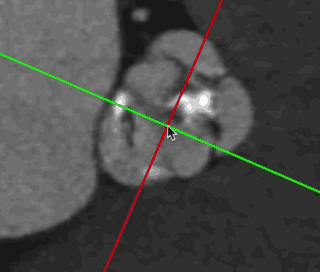

术前CT分析:

主动脉根部